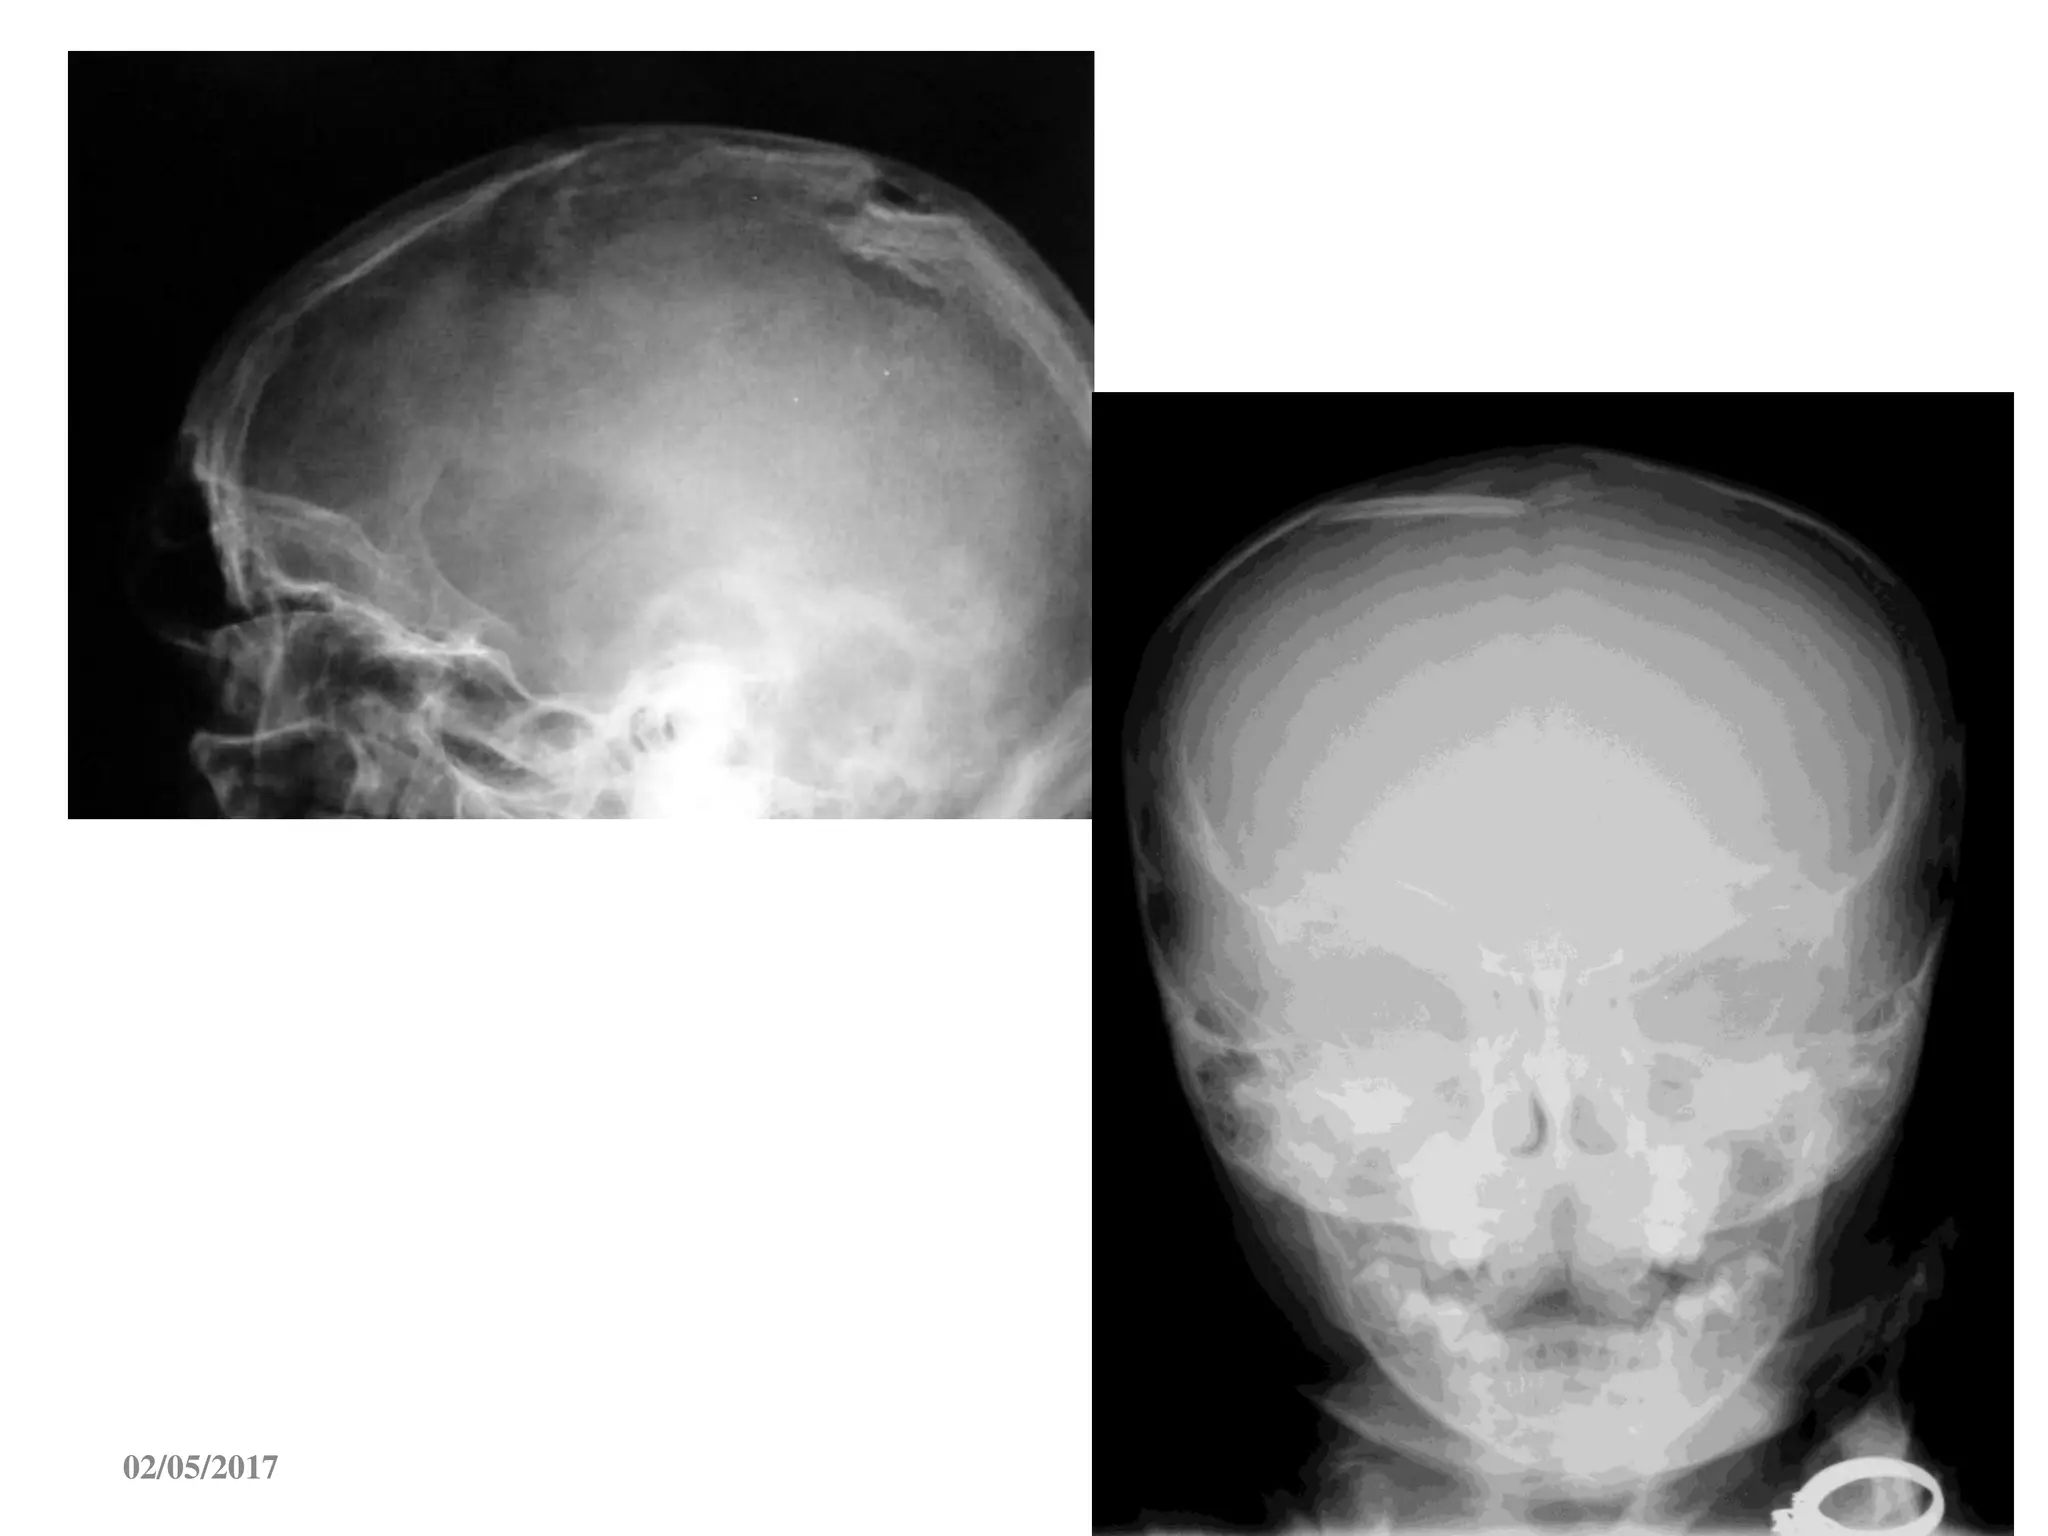

* Nöùt soï daïng ñöôøng (hay gaëp

nhaát) ; ñöôøng saùng, maát lieân

tuïc ôû baûn soï

* Luùn soï

* Daõn khôùp soï

* Vôõ vuïn vaø vôõ phöùc taïp

Vôõ xöông :

Neáu coù gaõy xöông  taêng khaû naêng toån thöông trong soï (#20 laàn)

Tuy nhieân, Xquang soï bình thöôøng vaãn coù toån thöông trong soï

(75%)

1. X QUANG SOÏ

* Nöùt soïdaïng ñöôøng (hay gaëp nhaát) ; ñöôøng saùng, maát lieân tuïc ôû baûn soï * Luùn soï * Daõn khôùp soï * Vôõ vuïn vaø vôõ phöùc taïp Vôõ xöông : 02/05/2017 69